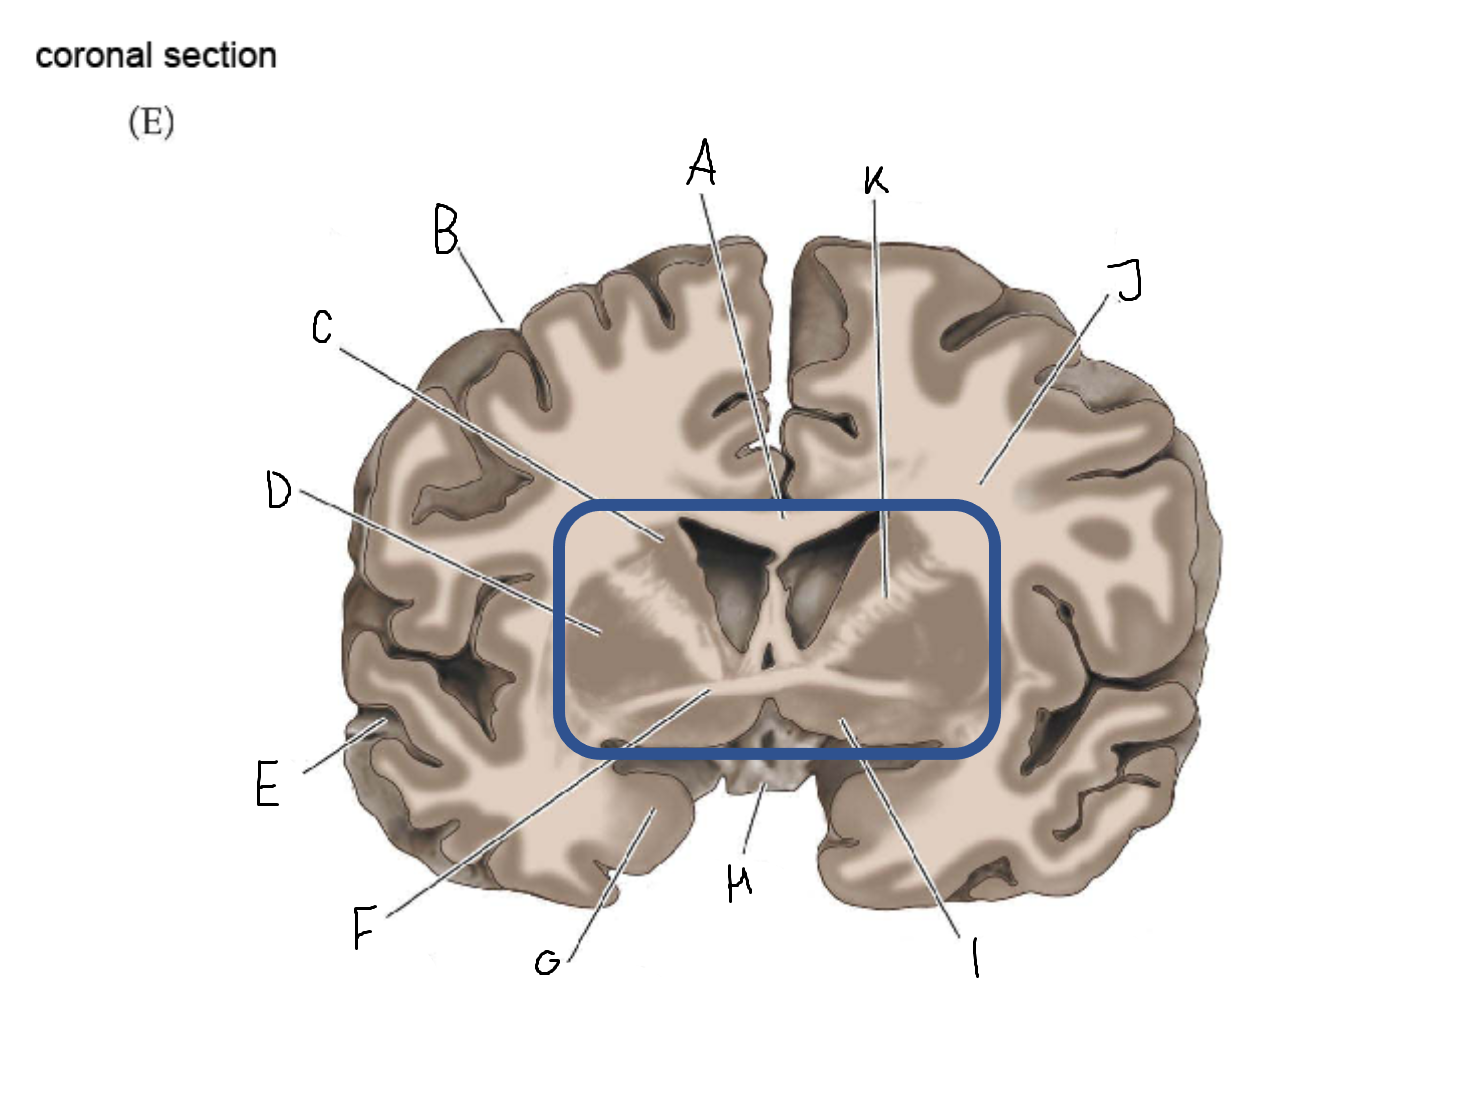

B

anterior horn of lateral ventricle

C

head of caudate nucleus

D

internal capsule (anterior limb)

E

putamen

F

globus pallidus

G

Thalamus

H

External capsule

I

internal capsule (posterior limb)

J

tail of caudate nucleus